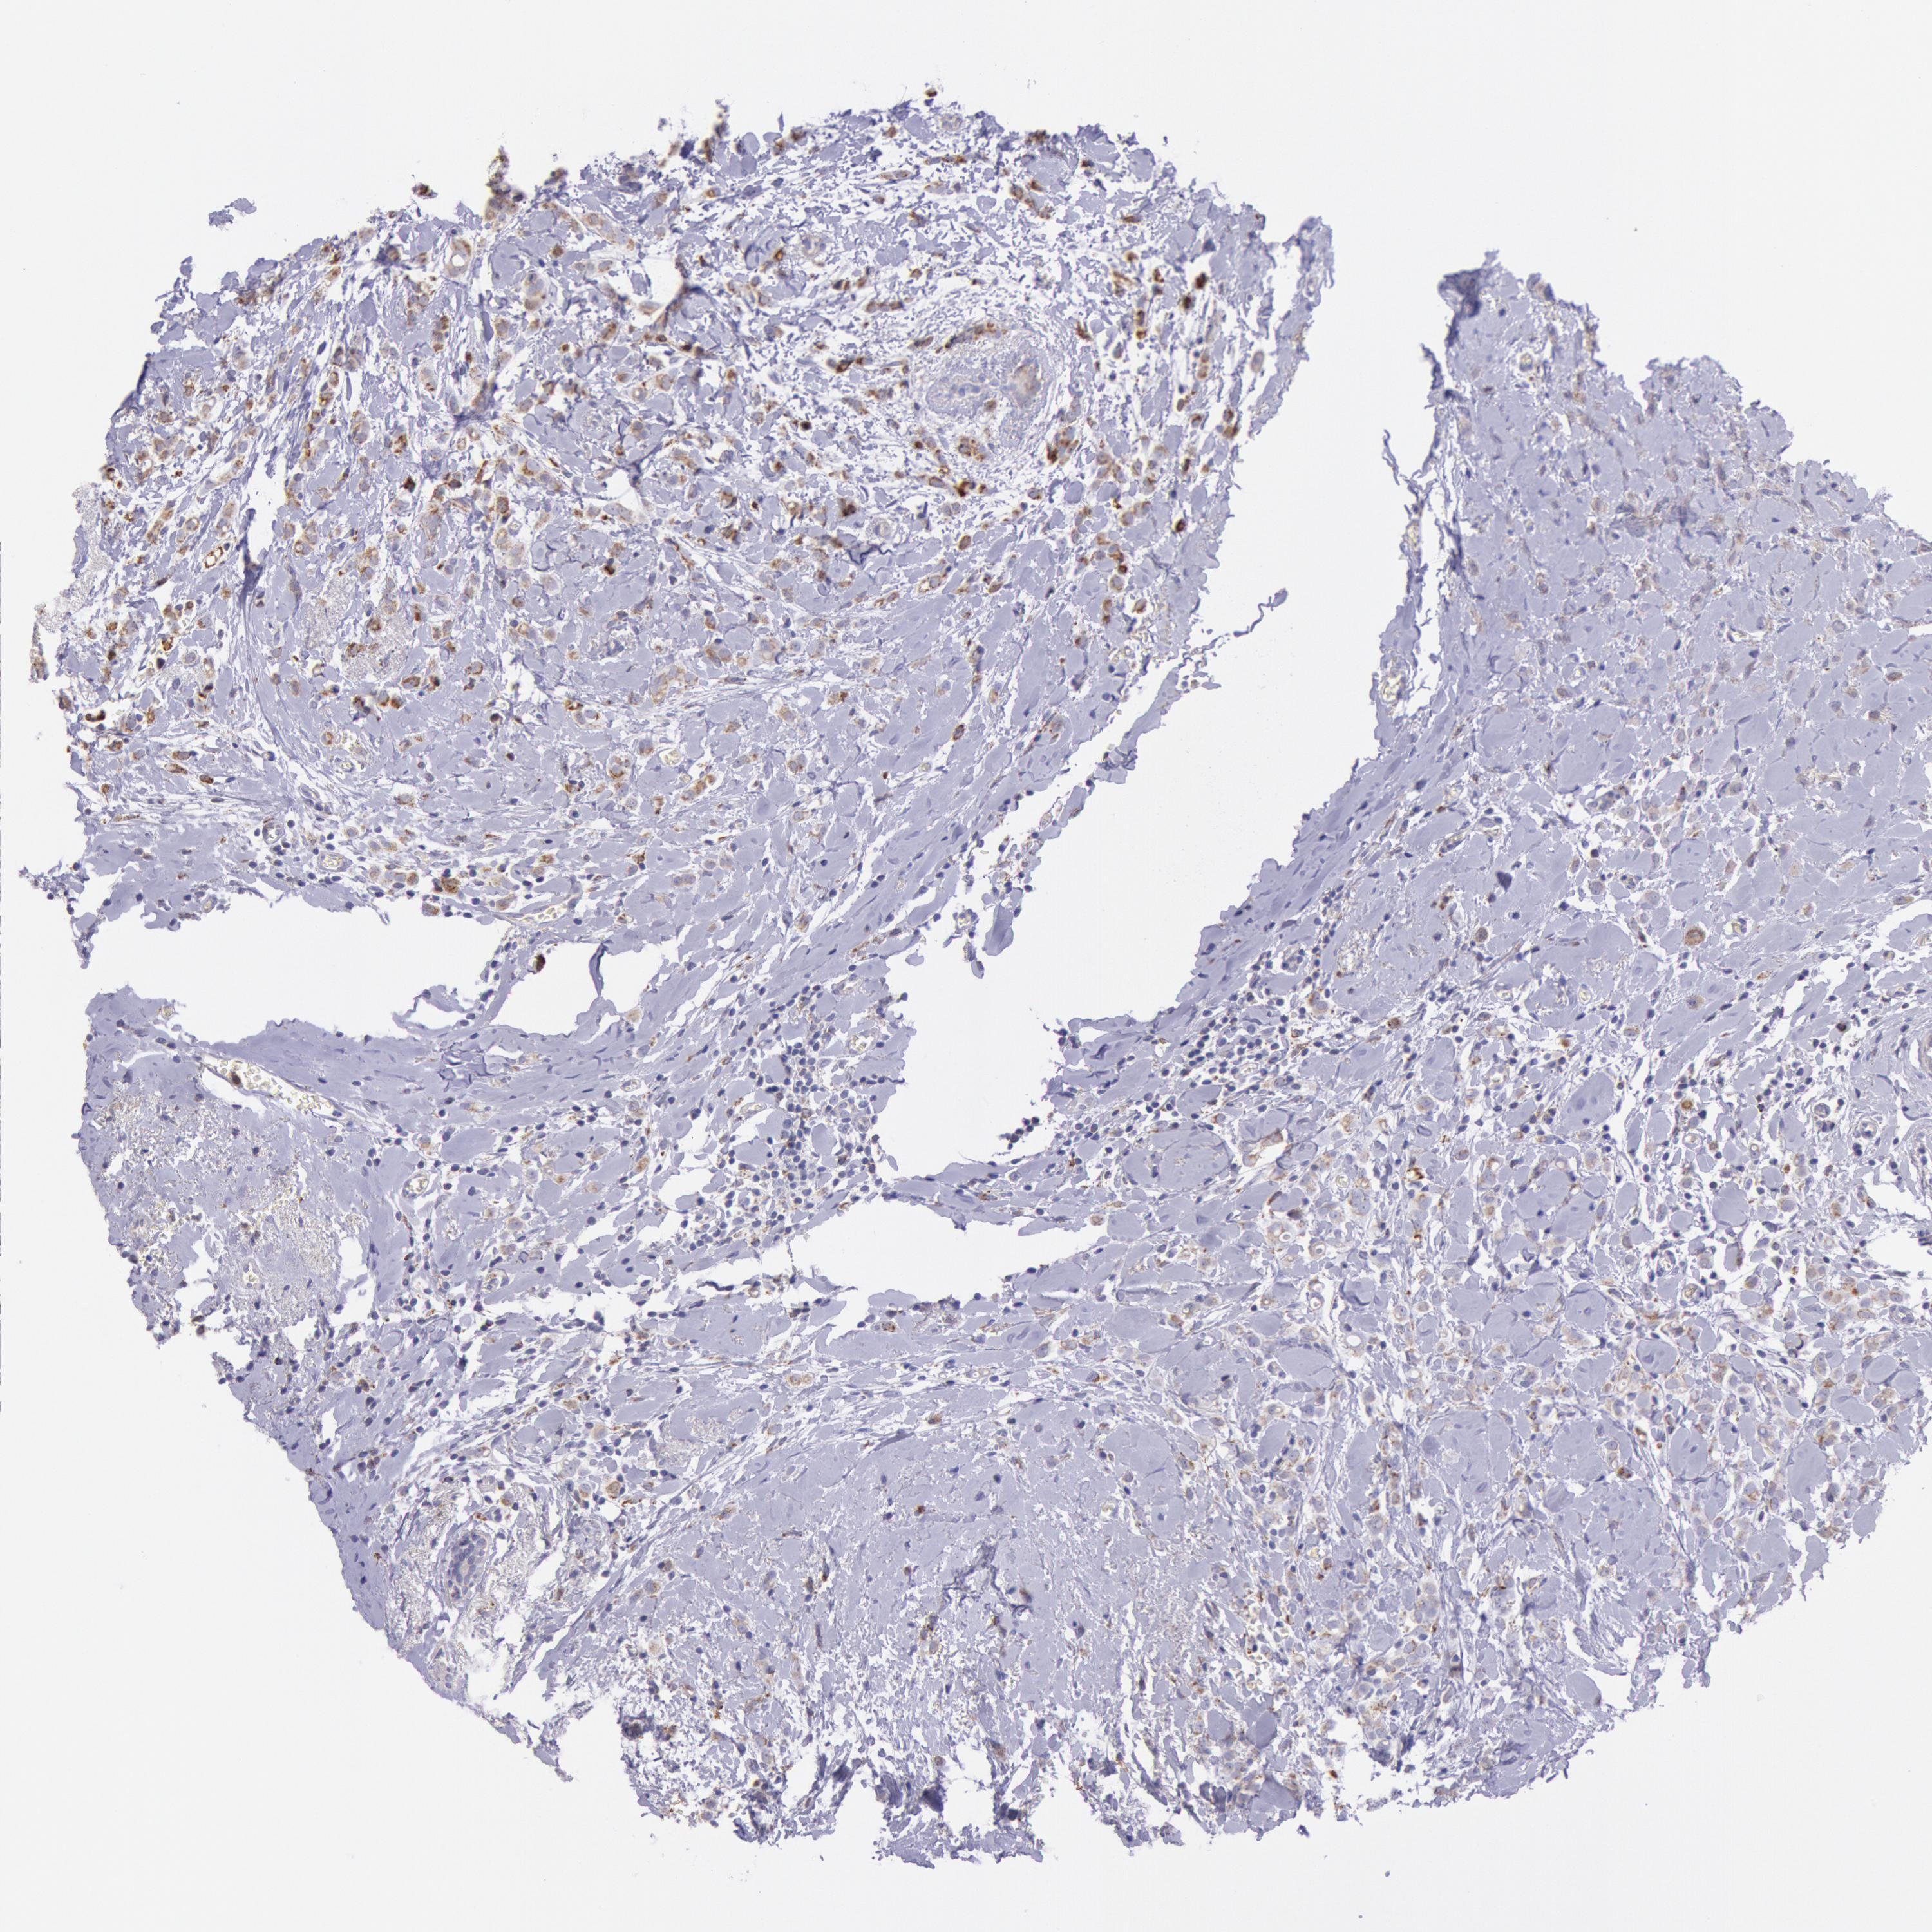

CANCER BREAST CANCER Show tissue menu

BRCA TCGA BRCA VALIDATION PROTEIN EXPRESSION